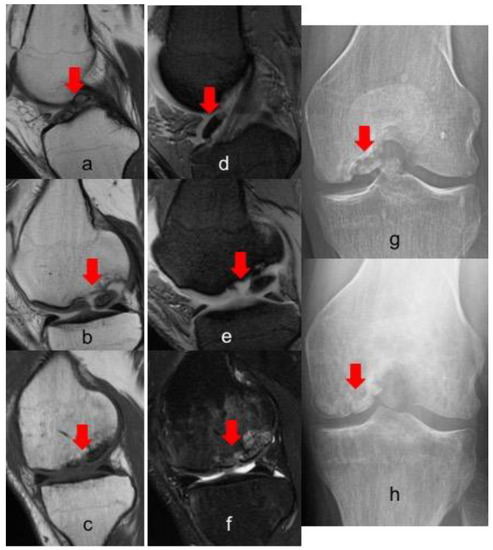

Postoperative radiographs and MRIs were used to classify and assess the healing of the treated lesion according to previously delineated criteria. (Figure 1, Figure 2 and Figure 3) A fluid interface between the OCD fragment and the condylar bone was considered a sign of incomplete consolidation. Then again, sclerosis or necrosis of the fragment were considered sign of non-consolidation [10,11].

Figure 3. MRI and X-ray evolution of a grade IV OCD of 4.6 cm2 in the medial condyle of a right knee fixed with three Smart Nails. (a,b) T1 preoperative sagittal view; (d,e) T2 preoperative sagittal view; (cf) 1 year postoperative sagittal view; (g) preoperative X-Ray; (h) 5 years postoperative X-ray. In all images the red arrow indicates the lesion, in figure a-d the red flag indicates a free intra-articular body.